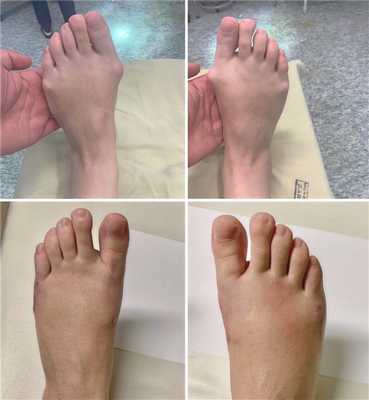

Фото до и после операции.

Отметим, что после операций на ступнях пациент не нуждается в ношении гипса и ходьбе с костылями. Уже на следующий день он может свободно вставать с постели, предварительно надев специальную обувь. В туфлях Барука больному необходимо ходить на протяжении нескольких недель после хирургического вмешательства.

Операция при плоскостопии позволяет быстро восстановить функции стопы. В большинстве случаев пациенты возвращаются к привычному образу жизни уже спустя 3 месяца.